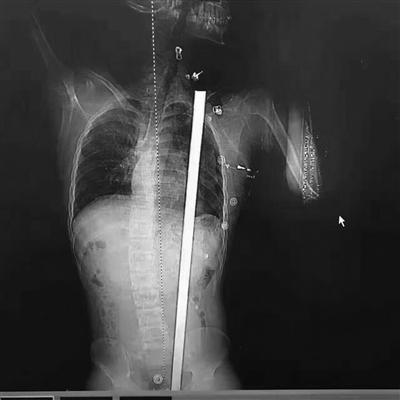

拍片顯示患者體內的鋼筋

“看到CT報告,我們發現鋼筋直達肩胛”。徐進宇說,從報告上看,鋼筋是從肛門旁進入,穿過腹部和胸部,所幸是從脾、胃、腎中間穿過,和心臟擦過,而且沒有傷及大血管。徐主任說,小楊非常幸運,這根鋼筋的走線都沒有觸碰到關鍵要害,如果傷到了致命血管,勢必造成大出血,病人往往都等不及送醫。